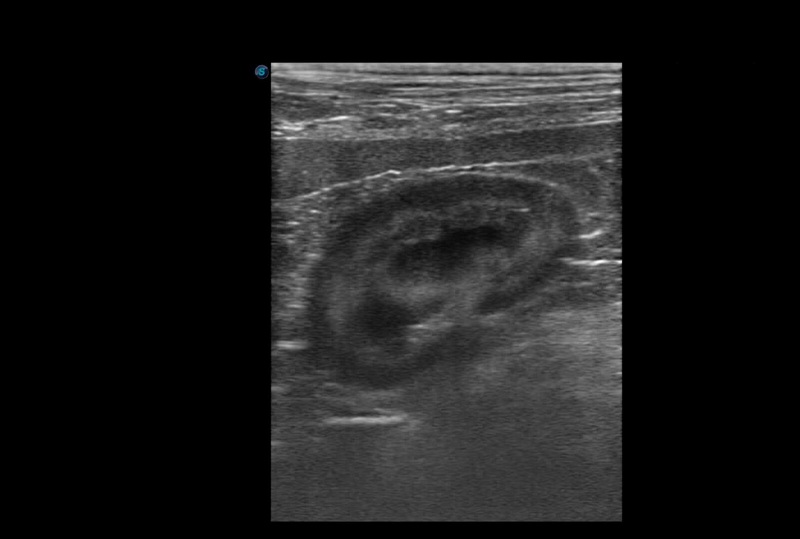

• 探頭,影像皆屬彩超等級處理配置

• 具備影像後處理功能